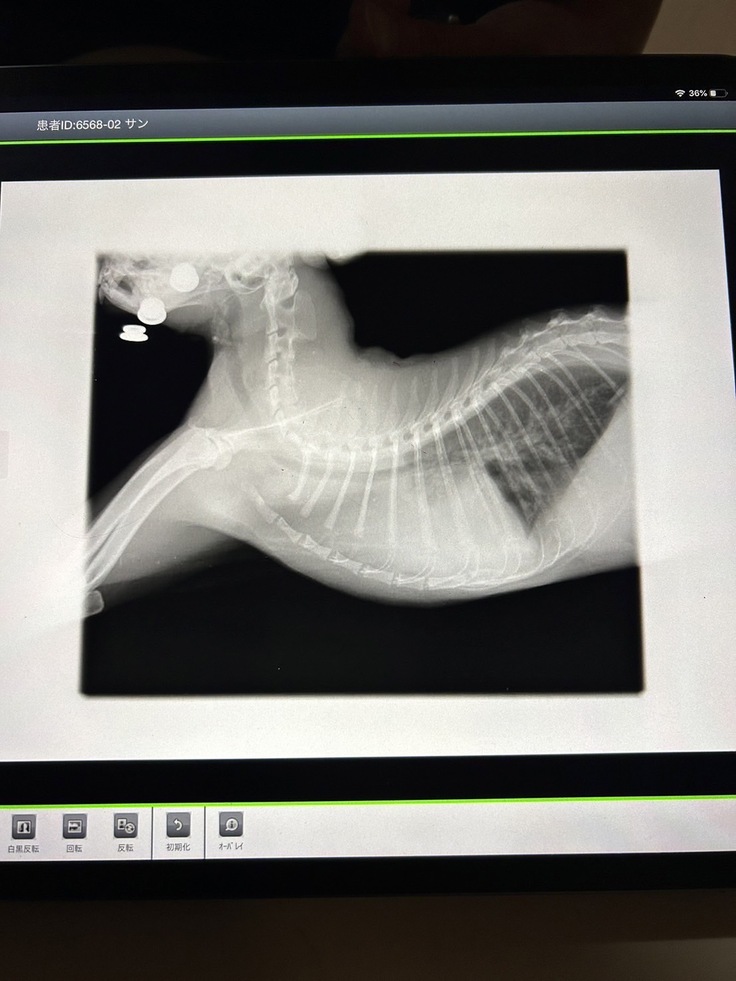

胸部、水が溜まっている所が白濁しています

3月に入ると、水が溜まる頻度、量が増え始め、2週間毎の通院を1週間毎にした方が良いと獣医師から言われました。

また、点滴の量が肺に溜まる水量に大きく影響する為、利尿剤の薬と伴わせながら合間を取る治療がこの先も続きます。

3月25日、専門病院にて診察していただき、サンくんの心臓は「肥大型心筋症stageC」と診断が下されました。

そして、腎臓は「慢性腎臓病」と診断されました。